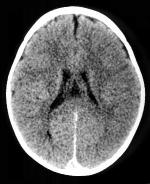

Een CT-scan van de hersenen kan uitgevoerd worden met of zonder

contrasttoediening. Welke methode gebruikt wordt is afhankelijk van de

indicatie. In sommige gevallen kan het aangewezen zijn het onderzoek

eerst zonder en daarna met contrast uit te voeren om een duidelijker

beeld te verkrijgen in de pathologie van de patiënt.